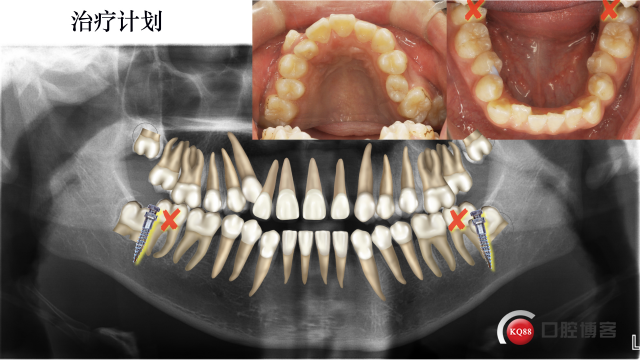

治疗计划:

拔除37,47,全口固定矫正,使用低转矩DamonQ金属自锁托槽,粘接全口托槽

42.41.31.32倒粘(托槽转矩从-11度变成+11度)、通过配合Damon含铜镍钛弓丝扩大上颌牙弓,在13和25处放置推簧,待推出足够空间在将13,25纳入牙弓。下颌排齐后在外斜线处植入2*10mmVector支抗钉整体远移下牙弓,调整磨牙尖牙关系及覆合覆盖问题。要求患者进行舌肌锻炼。